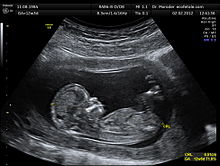

Most readers are familiar with ultrasound imaging of babies. A high-frequency signal is sent inside the body, and various tissues or tissue junctions reflect the signal at variable intensity. Based on received signal, the computer generates a picture of what is inside the body. The process is non- destructive provided the strength of signal sent inside body is low.